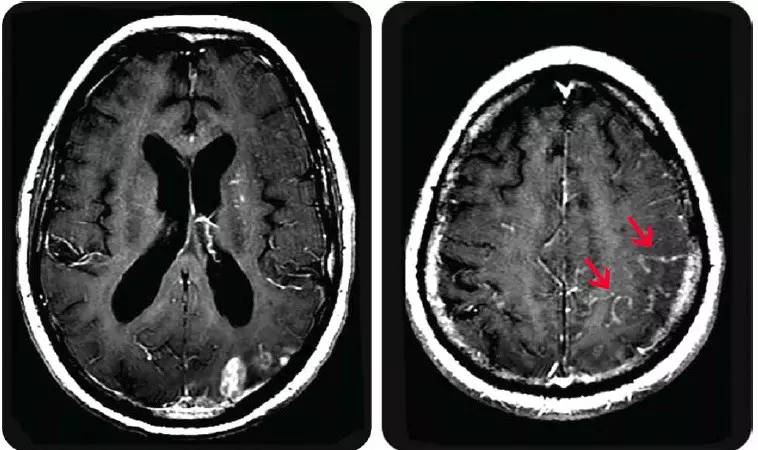

增强扫描显示软脑膜强化(主要位于左侧额颞),提示蛛网膜下腔内的血管受累。